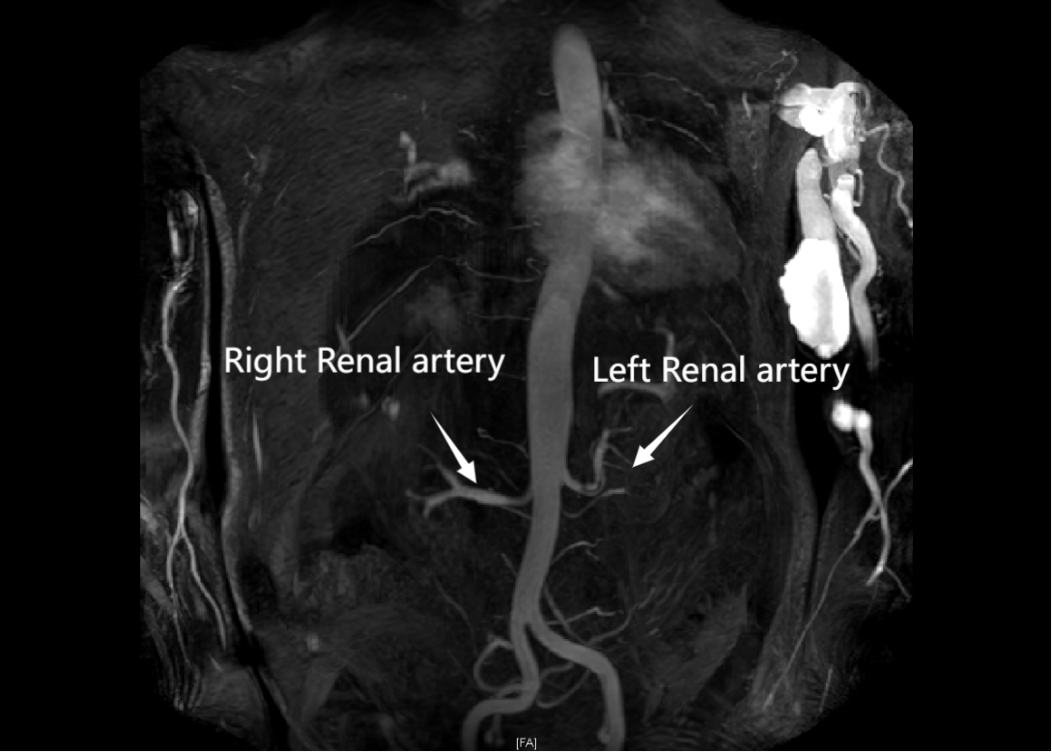

患者在无尿期间仍有持续性镜下血尿(发病前记录显示)。无尿前期进行的肾活检显示:弥漫性全球性肾小球硬化,无活动性肾小球肾炎。全面的自身免疫学检查均为阴性。影像学检查(包括CT扫描、多普勒超声及磁共振血管成像)已排除结构性病因(

图1 腹部磁共振血管成像显示肾脏未见血管性或解剖结构异常